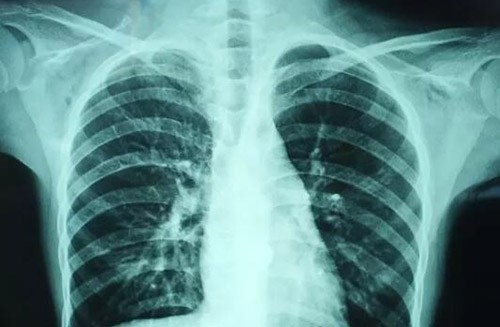

关于新型冠状病毒肺炎,你关心的都在这里